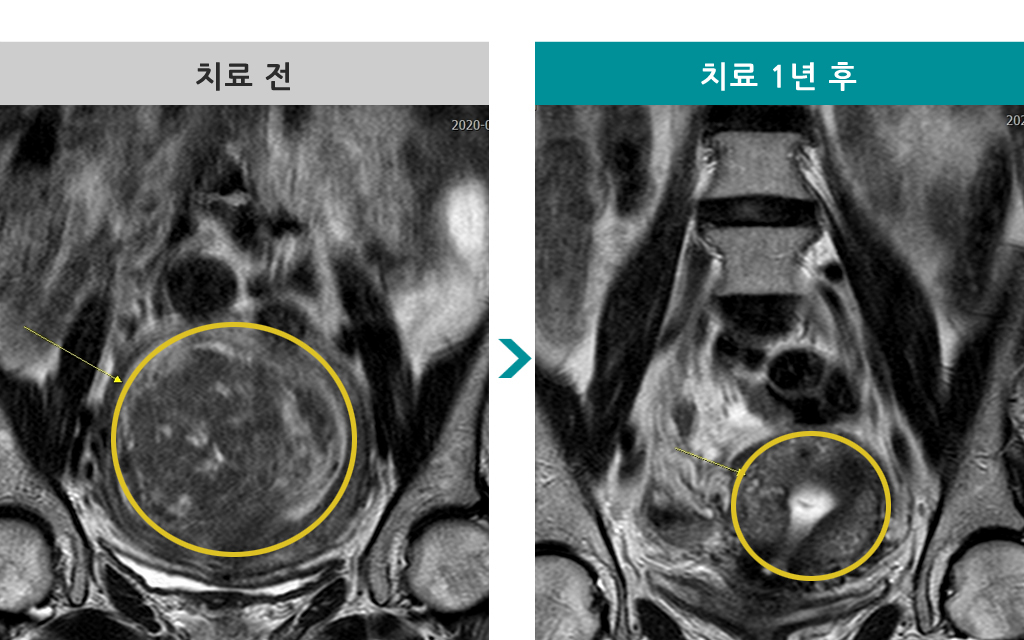

51세 [자궁근종 색전술] 전후 MRI사진 비교